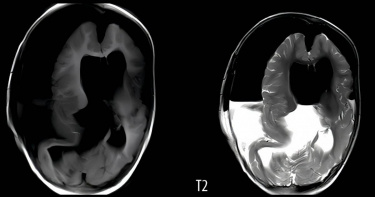

23歲女情緒異常波動接受抑鬱症治療6年 住院竟驚見嚴重「腦積水」

加利福尼亞23歲女子克洛伊(Chloe Kral)由於情緒過度波動,被診斷患有嚴重抑鬱症,因此接受精神科治療整整6年,不過病症卻越來越嚴重,近年甚至惡化成短期記憶力喪失、無法控制四肢等,家人為此將他送進心理治療機構住了6個月,直到克洛伊被送進醫院急診室,透過電腦斷層才赫然發現她患有腦積水,透過手術將其清除後,不但情緒問題消失,她也重新回歸日常生活。根據《每日郵報》,克洛伊從2016年10月開始,偶然間突然出現情緒方面問題而逃課整整6週時間,她也從此踏上精神科治療之路,在接下來的6年間,克洛伊飽受情緒波動之苦,即使持續服用精神科醫師開的抑鬱症藥物,病情仍不見任何起色,甚至惡化到出現記憶問題。美國加利福尼亞女子克洛伊長期受精神問題所苦,沒想到經過電腦斷層診斷,才發現她有嚴重腦積水。(圖/翻攝自推特)克洛伊透露,患病初期她還在一所社區大學上課,但因為記憶問題,她一直忘記要交作業,還因為記不住指令而丟了工作。2019年克洛伊開始會突然暴怒,出現攻擊性舉動,接著還漸漸不能控制右腳,走路一跛一跛的;當年秋天,克洛伊不但會忘記刷牙、洗澡,整天只躺在客廳沙發上發呆,還會做出如在車裡弄濕自己的奇怪舉動。克洛伊被診斷出嚴重腦積水。(圖/翻攝自《每日郵報》)2020年9月,眼見克洛伊情況越來越糟,家人將她送進當地心理治療機構,砸了約18萬美元(約新台幣527萬)進行為期6個月治療,直到醫生替她看診時直覺「不對勁」,因此進行腦部斷層檢查,這才發現克洛伊腦積水情況嚴重,趕緊聯絡神經外科進行手術。手術後克洛伊恢復極快,隔天克洛伊便打電話給母親,請她帶一些雜誌到病房,3個月後,她已經可以完全獨立生活,不但可以開車、工作,也重新申請大學,目前正在舊金山一間設計學院上學。克洛伊表示「對我來說,醫院的治療讓我有機會將我一直以來嚮往的生活化為現實,我很感謝」。克洛伊在接受手術後,已經回歸日常生活。(圖/翻攝自臉書)